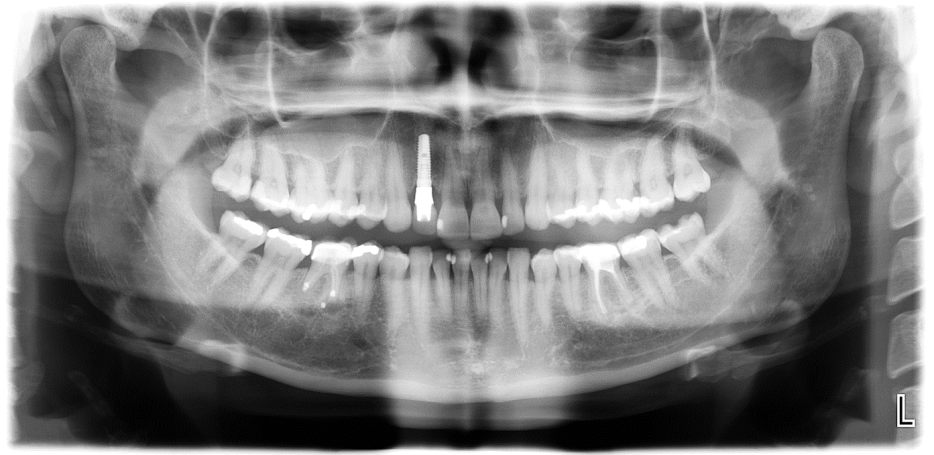

In unserer Praxis arbeiten wir mit DVT dreidimensionalen Röntgenbildern, um den Grad der Entzündungen des wurzelkanalbehandelten Zahns genau zu bestimmen.

In bestimmten Fällen, wird zusätzlich eine CaviTau- Aufnahme und ein Labortest „Effektorzelltypisierung auf Mercaptane und Thioether“ gemacht. (Die Effektorzelltypisierung auf Mercaptane und Thioether zeigt durch die Zytokine (TH1-IFN-γ /Treg-IL-10)

an, ob zum aktuellen Zeitpunkt eine Immunreaktion gegen diese Substanzen stattfindet.)